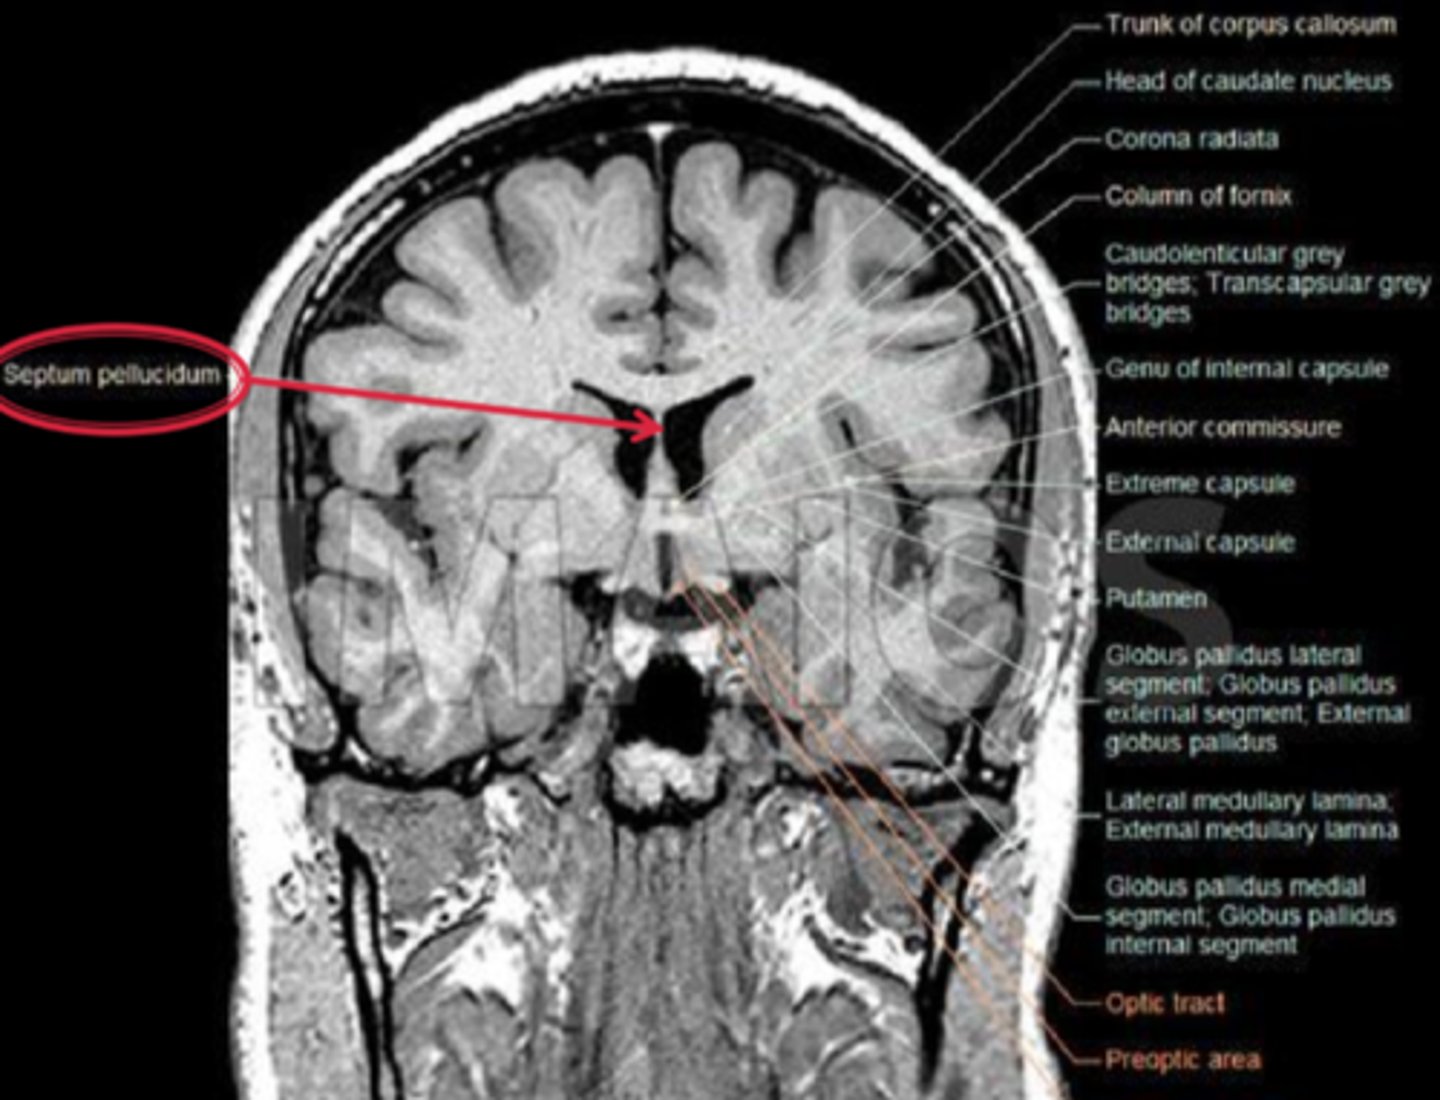

What are some associations seen in pt's with bilateral hypoplasia of their ONH and poor VA?

developmental abnormalities like GH deficiency, hypothyroidism

forebrain anomalies such as lacking a septum pelucidum between the 2 lateral ventricle halves

What is De Morsier's syndrome?

septo-optic dysplasia with...

bilateral ONH dyplasia

absence of septum pellucidum

agenesis of corpus callosum

dysplasia of 3rd ventricle

hypopitutitarism